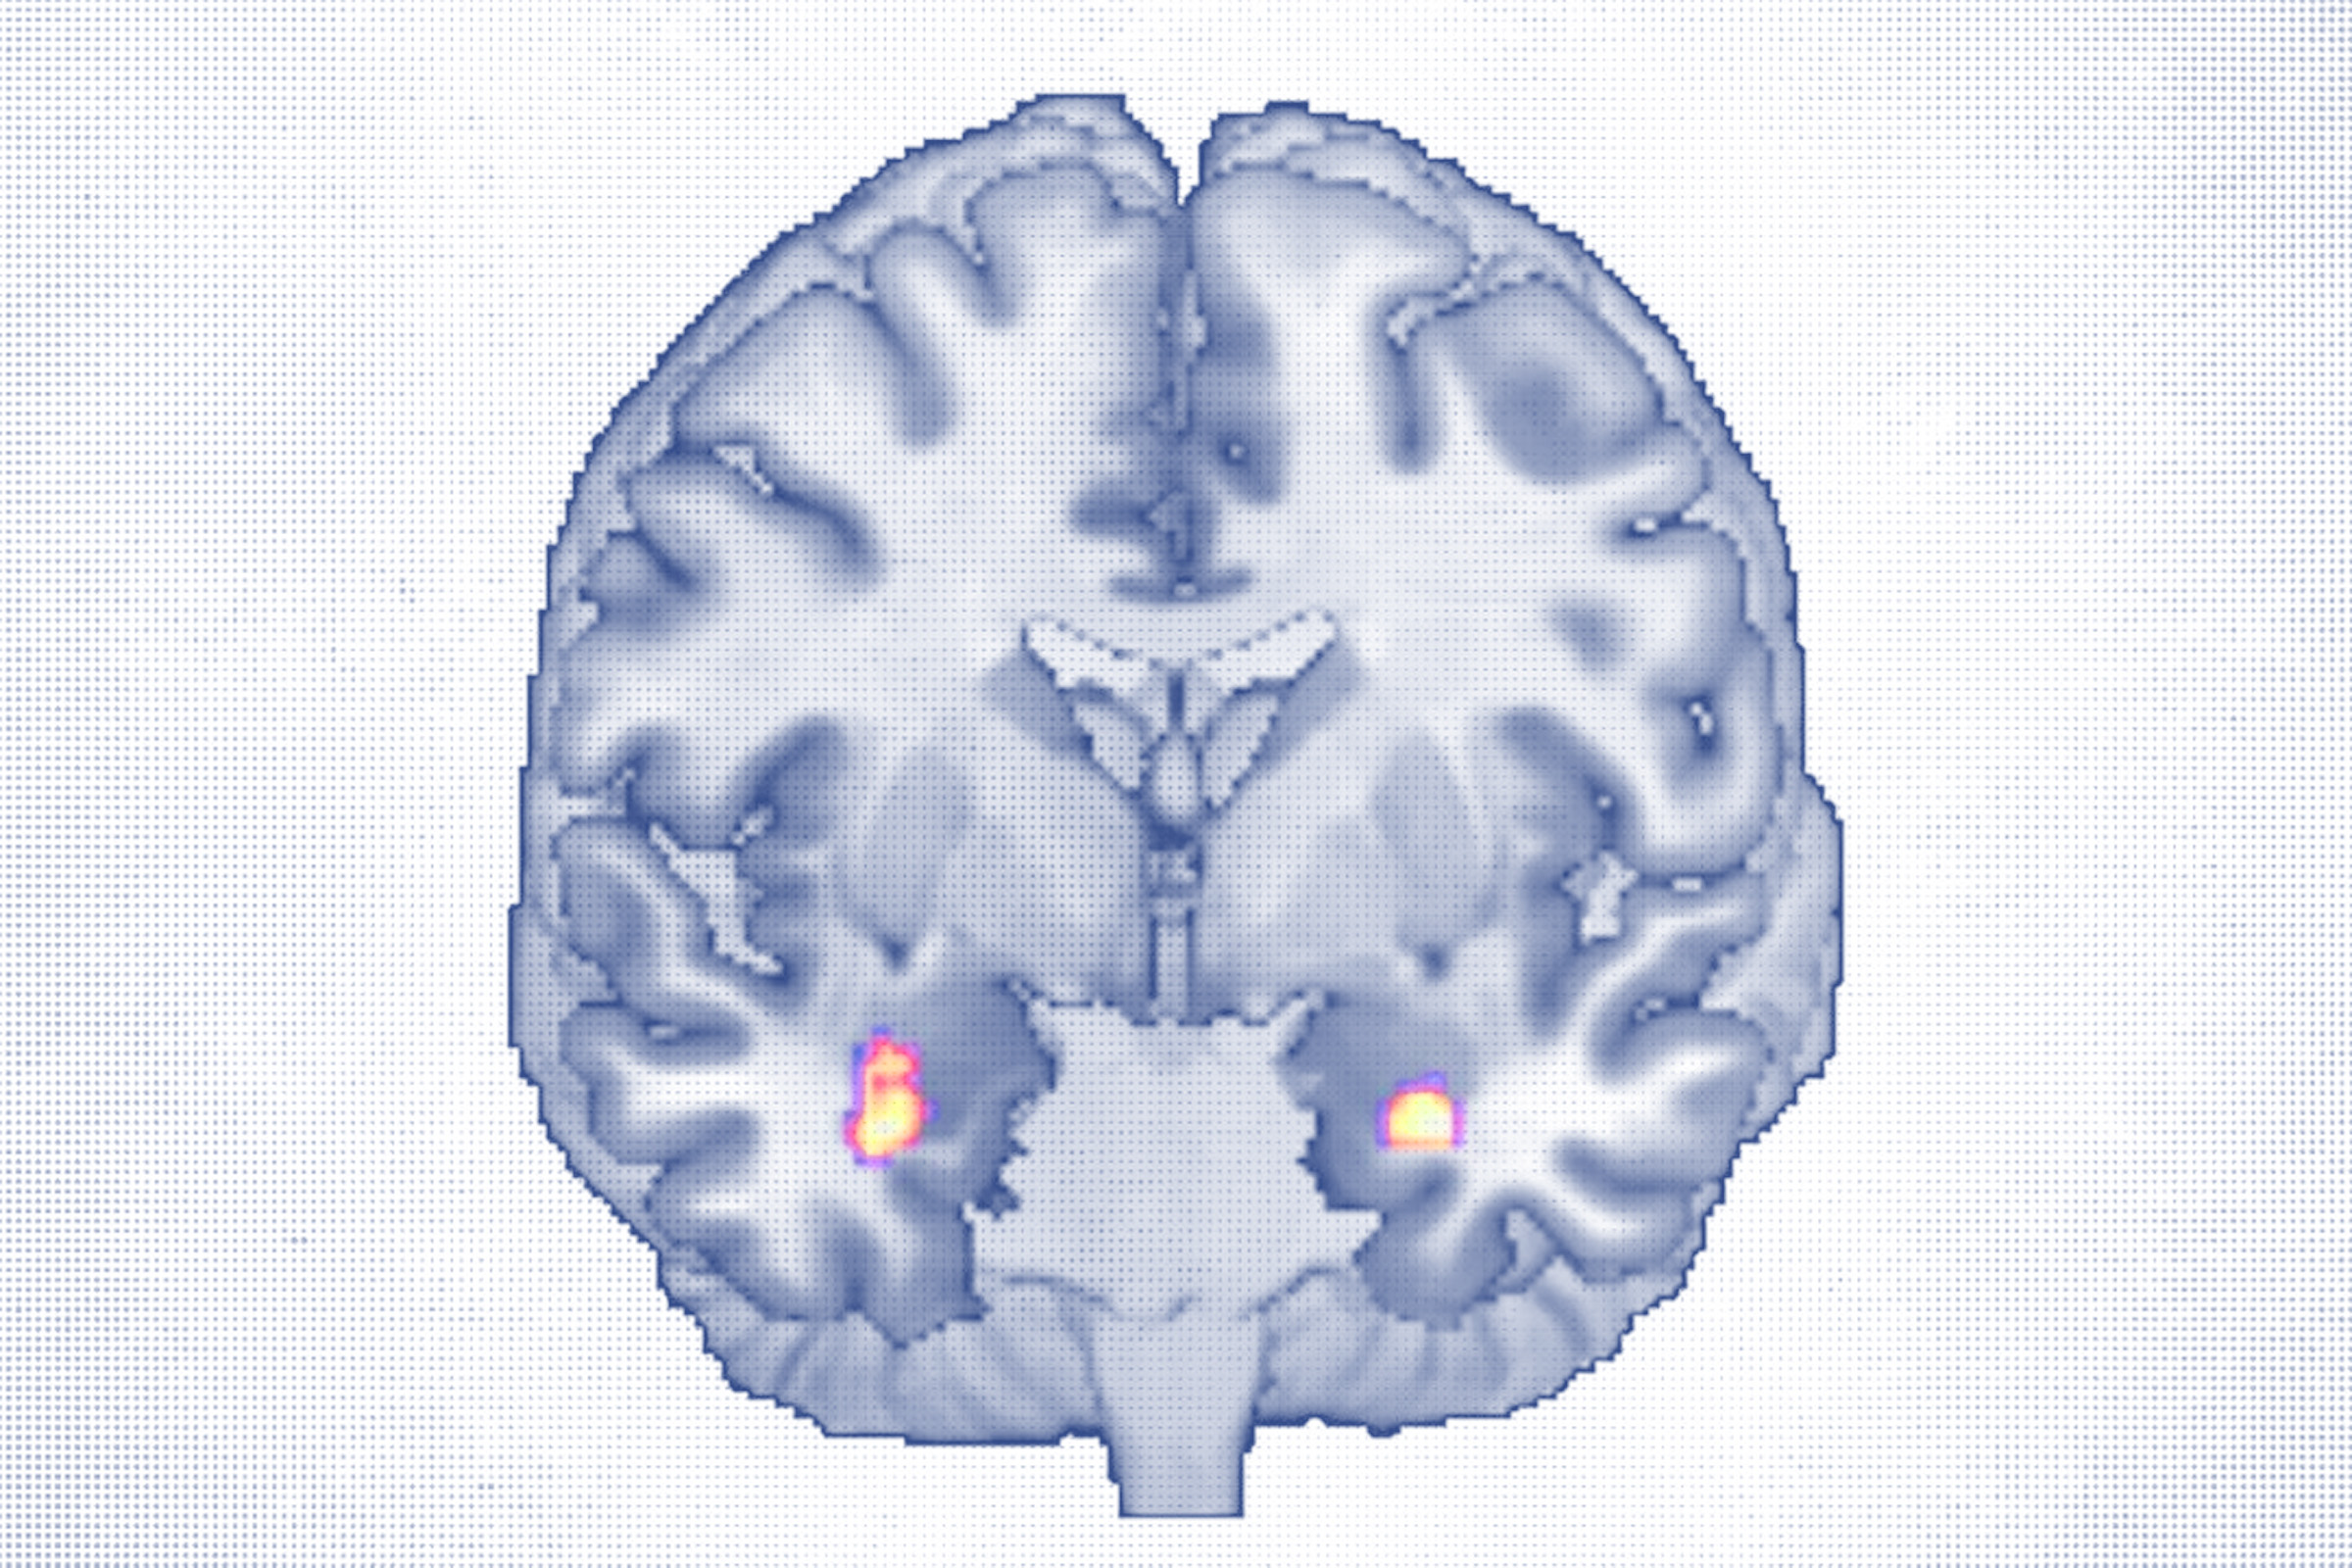

A brain imaging study published in Translational Psychiatry found that adults who completed a course of cognitive behavioral therapy (CBT) showed measurable growth in regions of the brain responsible for emotion processing and mood regulation. These areas, often weakened in chronic depression, appeared to strengthen over the course of treatment.

The study followed 30 adults, ages 18 to 65, with major depressive disorder who received about 20 CBT sessions over 40 weeks. High-resolution MRI scans before and after treatment revealed increased gray matter volume in the amygdala, a key region for emotional processing, and the anterior hippocampus, which is involved in memory and mood regulation.

Both areas are known to shrink in people with depression, so growth here may signal recovery, the researchers noted.

Increased gray matter in the amygdala was correlated with a greater ability to perceive emotions, particularly one’s own, Redlich said.